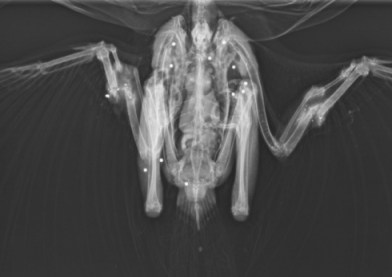

A veterinary x-ray revealed a peppering of shotgun pellets throughout its body resulting in the bones of both wings being smashed.

A member of the public found the wounded bird by the roadside on 2nd January 2014 and took it to the Larwood and Kennedy Veterinary Practice in Dereham. Vets believed the bird had been shot several days before it was picked up and due to the extent of its injuries the buzzard was euthanised.

Vet George Gould, who examined the bird, said: “These sorts of injuries in particular do not tend to be immediately fatal but instead result in days of suffering”.